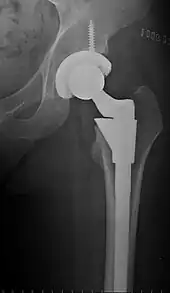

Hip replacement is a surgical procedure in which the hip joint is replaced by a prosthetic implant, that is, a hip prosthesis. Hip replacement surgery can be performed as a total replacement or a hemi/semi(half) replacement. Such joint replacement orthopaedic surgery is generally conducted to relieve arthritis pain or in some hip fractures. A total hip replacement (total hip arthroplasty or THA) consists of replacing both the acetabulum and the femoral head while hemiarthroplasty generally only replaces the femoral head. Hip replacement is one of the most common orthopaedic operations, though patient satisfaction varies widely. Approximately 58% of total hip replacements are estimated to last 25 years.[1] The average cost of a total hip replacement in 2012 was $40,364 in the United States, and about $7,700 to $12,000 in most European countries.[2]

Configuration

Post-operative projectional radiography is routinely performed to ensure proper configuration of hip prostheses.

The direction of the acetabular cup influences the range of motion of the leg, and also affects the risk of dislocation.[9] For this purpose, the acetabular inclination and the acetabular anteversion are measurements of cup angulation in the coronal plane and the sagittal plane, respectively.